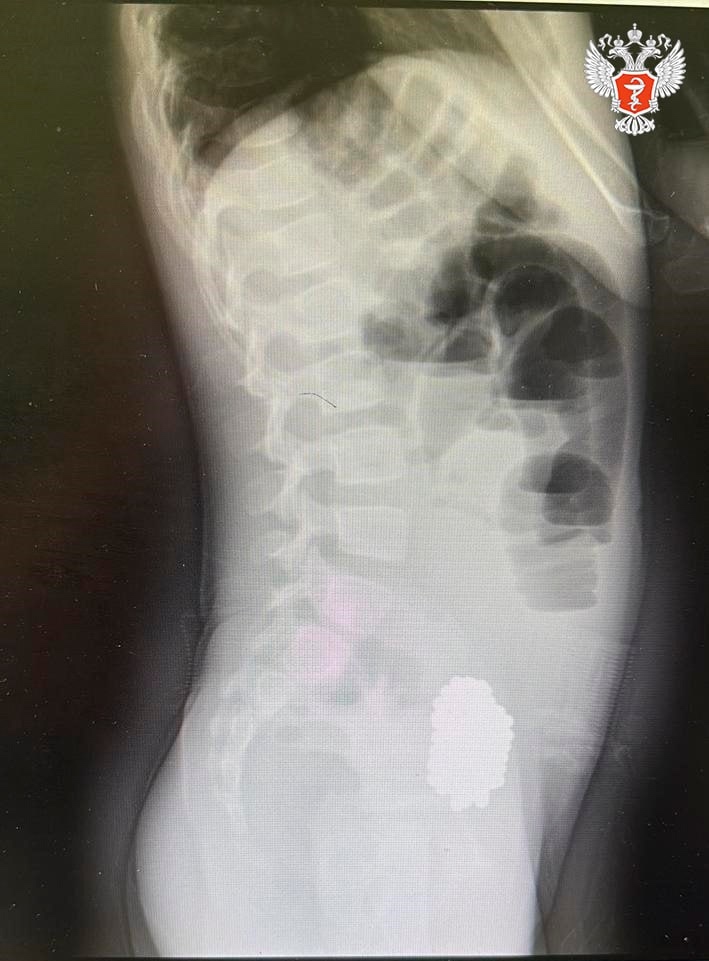

В ходе обследования врачи выявили кишечную непроходимость, вызванную инородным телом. Рентген показал массивный конгломерат из 134 магнитных шариков, которые сдавливали стенки кишечника.

❤️ Специалисты успешно провели лапароскопическую операцию и аккуратно извлекли магниты. Сейчас девочка чувствует себя хорошо.